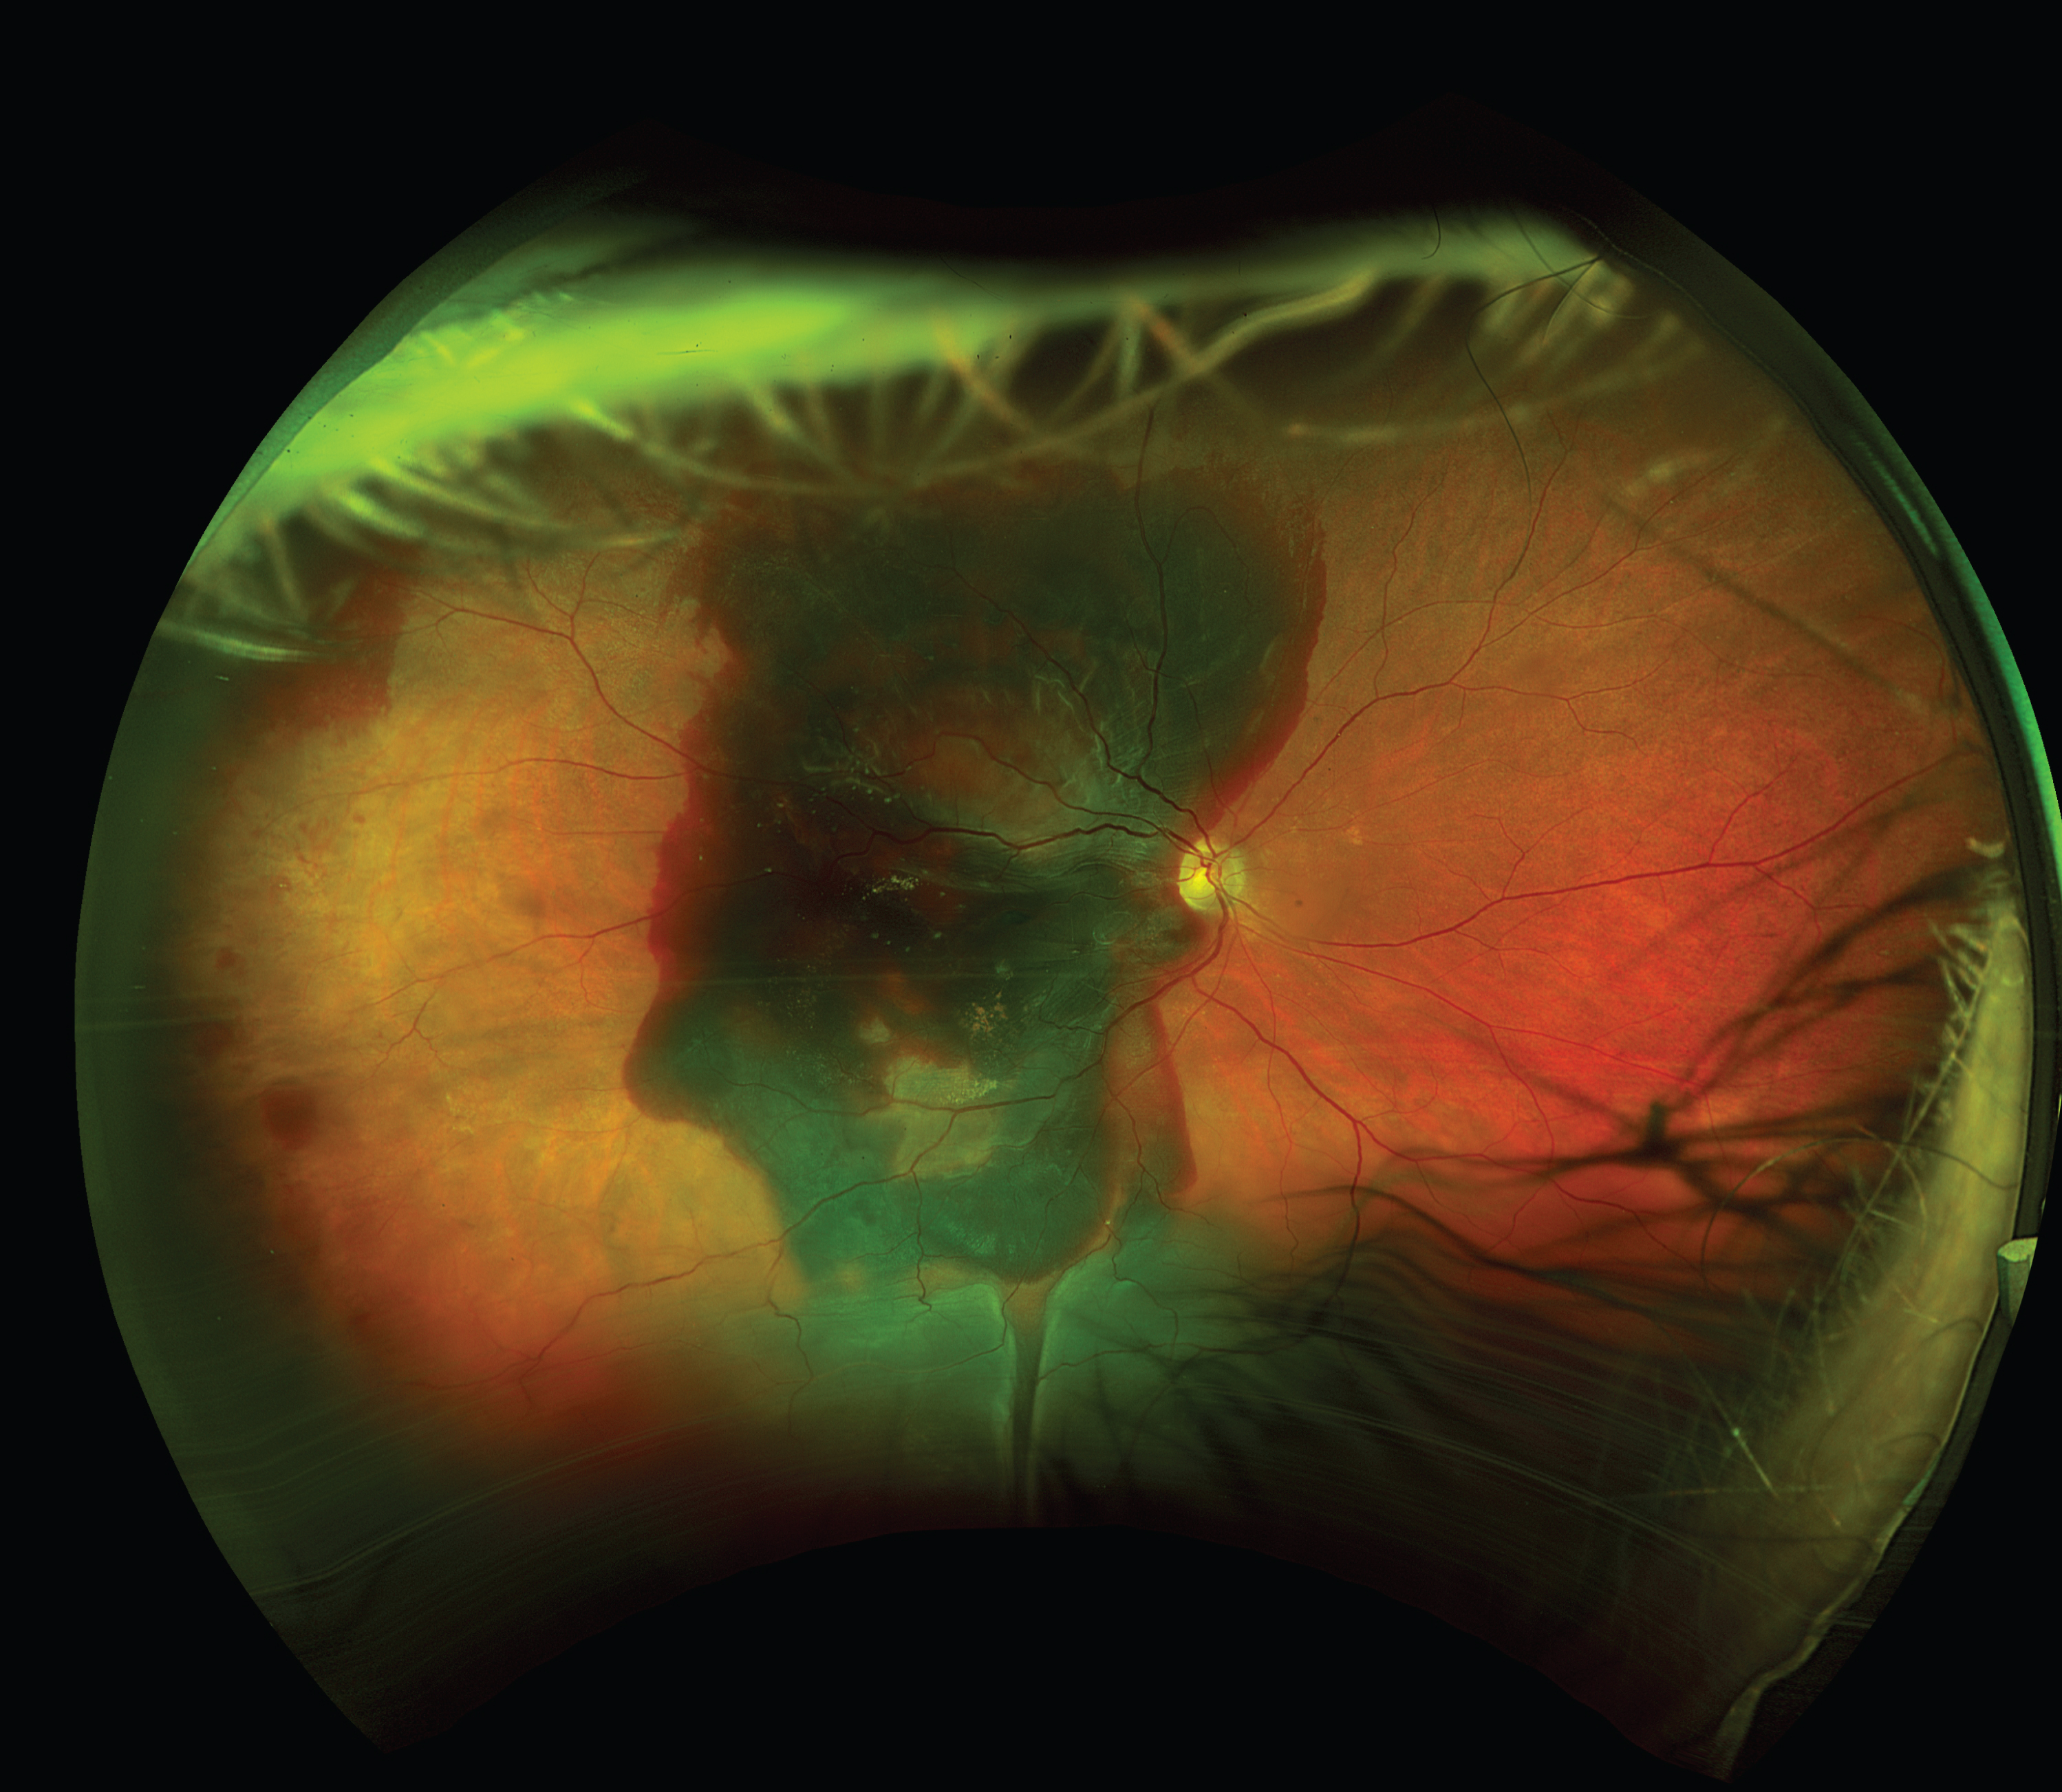

This is a widefield colour fundus photograph of the right eye of an 83-year-old patient with wet AMD. The image shows extensive subretinal haemorrhage involving the macula and extending superiorly and inferiorly with serous retinal detachment inferiorly as a complication of wet AMD. Best corrected visual acuity dropped from 6/9 to HM. The patient underwent Intravitreal injection of Tissue plasminogen activator (tPA), ranibizumab and C3F8 gas to displace the blood from the macula (Figure 1).